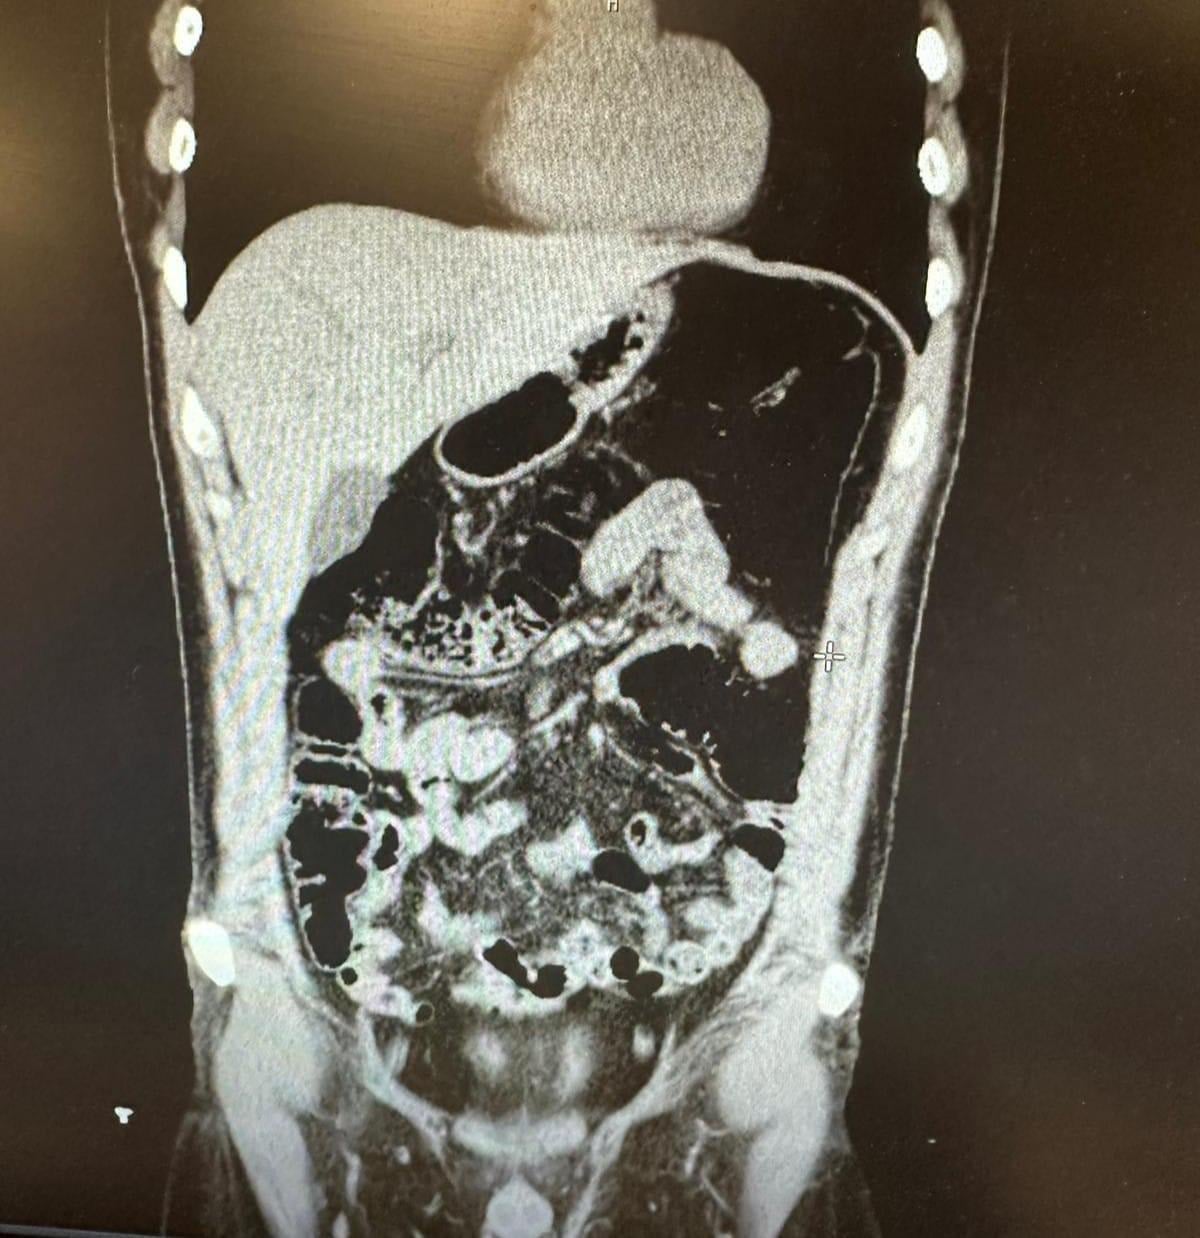

Şüpheli, uyuşturucu yuttuğunu ifade etmesi üzerine hastaneye kaldırıldı. Şüpheli, 2 gün boyunca polis nezaretinde hastanede gözlem altında tutularak midesinde kapsüller halinde bulunan eroin maddesi doğal yollarla dışarı çıkarıldı.

Konya’da konakladıkları evin tespit edilmesiyle 1’i İran uyruklu 5 şüpheli yakayı ele verdi. İran uyruklu V.F.G.’nin midesinde 300 gram, gizlendiği adreste Narkotik köpeği Alex ile yapılan aramada ise toplam 6 parça halinde 1 kilogram eroin, bir miktar metamfetamin ve bir miktar uyuşturucu hap ele geçirildi.